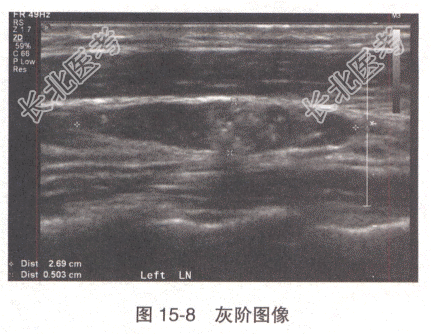

患者,女性,45岁。左颈部触及结节来诊。超声检查示左颈中部见一淋巴结,其声像图表现见图15-8、图15-9。

- 多项选择题1.对于该淋巴结的超声,叙述准确的是

A、中高回声团内见多个点状强回声

B、皮质内见中高回声团

C、髓质增厚,内见中高回声团

D、CDFI示中高回声区血流信号增多,分布不规则

E、髓质变薄,皮髓分界欠清

F、CDFI示淋巴结内血流分布规则,呈放射状

G、中高回声团边界不清